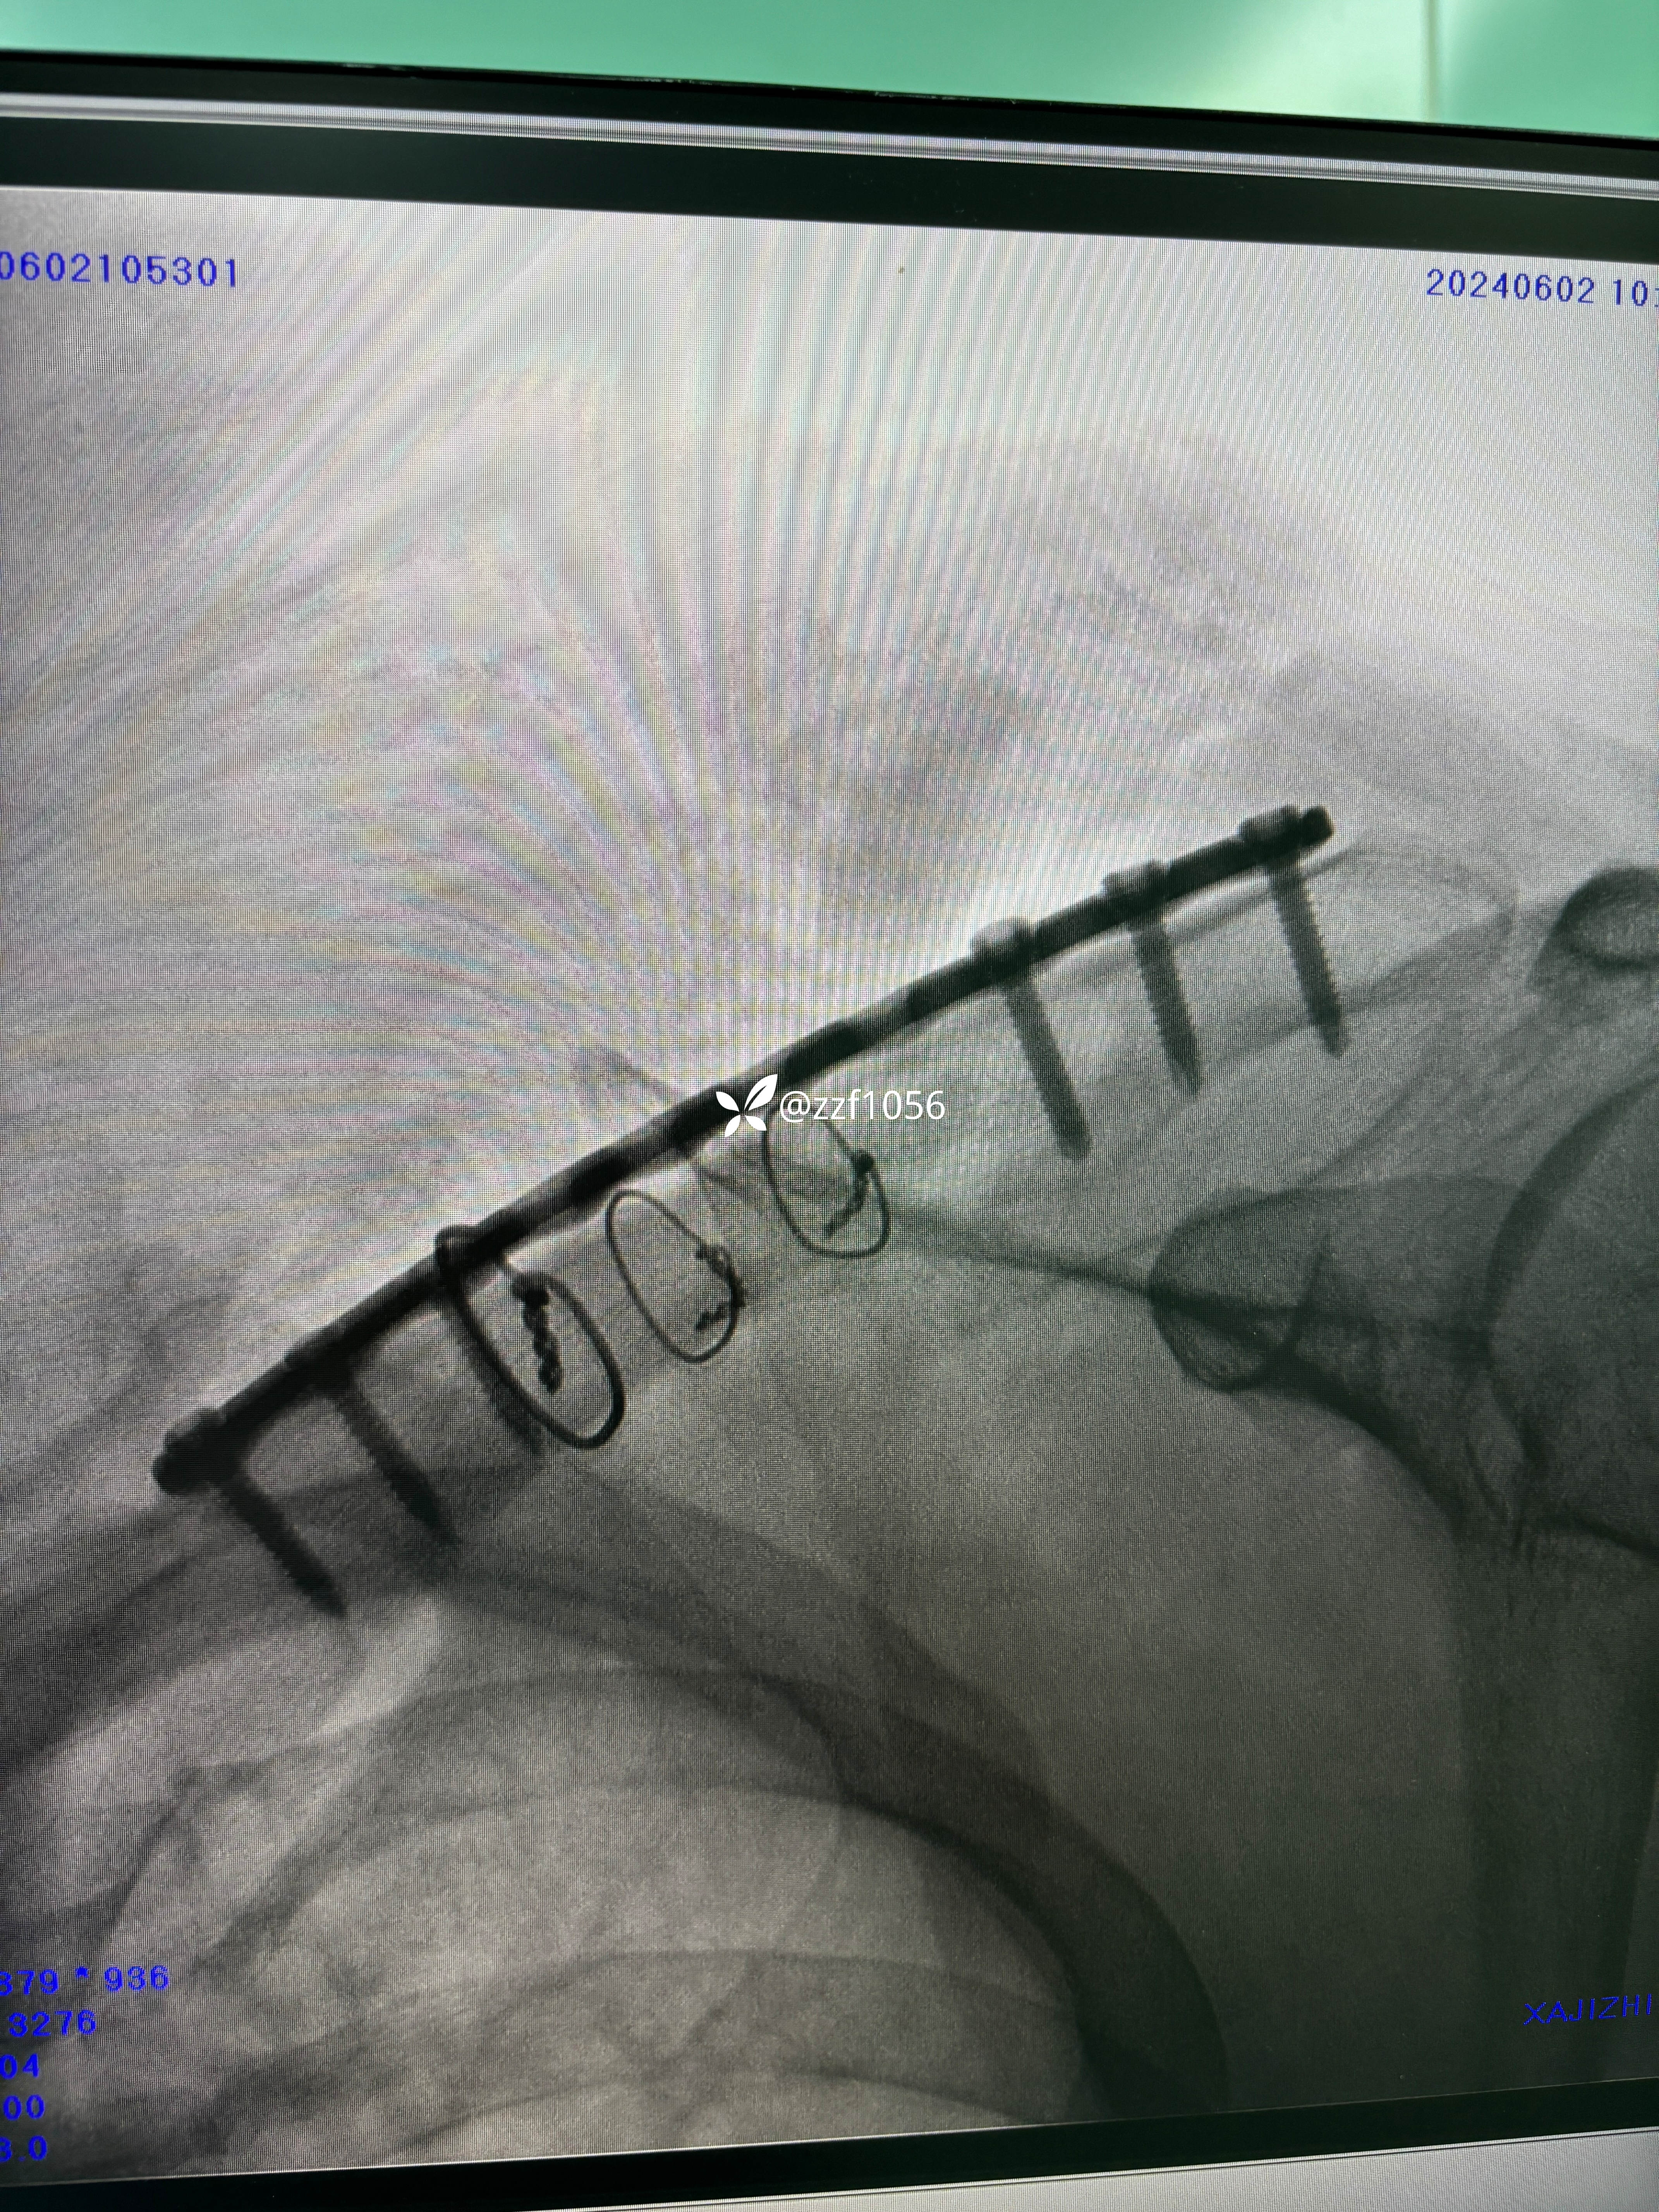

术中作切口后探查未见皮神经,保护好骨膜,清理折端复位临时克氏针固定,后方蝶形骨块较大,nice结改2道钢丝捆扎,复位良好,取最长10孔钢板,貌似钢板有点短,远折端3枚锁定螺钉有效固定,近折端只有2枚螺钉有效固定,第3枚螺钉失效且后方仍有骨块微翘,无奈增加一枚钢丝适宜捆扎。